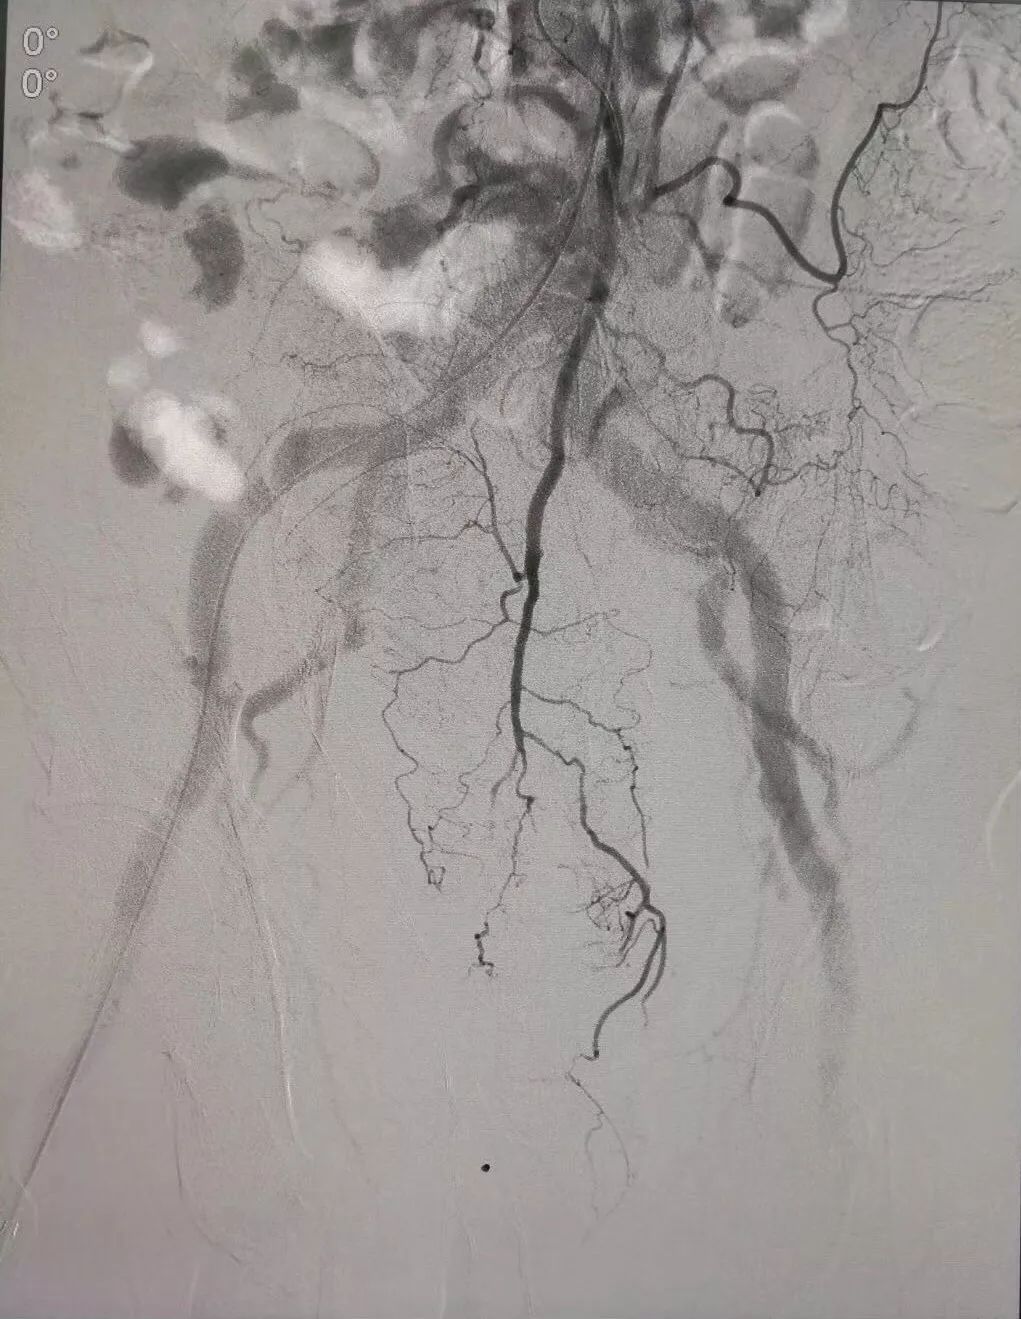

(肝静脉-门静脉穿刺成功,门脉高压,门静脉扩张明显)

(肝静脉-门静脉支架置入搭桥术,分流门脉部分血流,门脉压力降低)